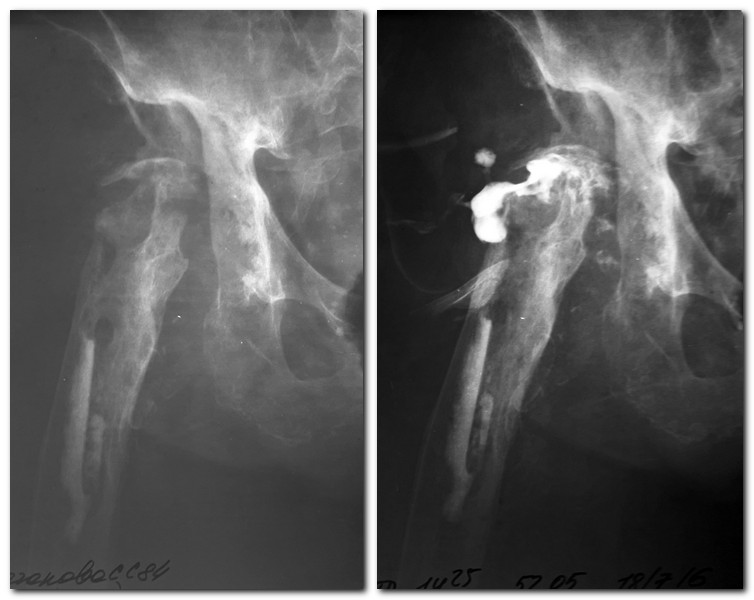

Уважаемые коллеги! Больная,84 года,удаление протеза тазобедренного сустава в 2014 году,парапротезная инфекция.2 года свищей не было. Пациентка активна, признаков деменции нет. До удаления протеза преподавала в ВУЗе. Ходила и ходит(пришла сама) с опорой при помощи ходунков с коррекцией укорочения ортопедической обувью. В канале остатки костного цемента. Удалить его тогда не удалось. Со слов больной на прошлой неделе вскрылся свищ, большое количество гнойного отделяемого выделилось. В настоящее время такая картина( Rn-грамма,фистулография).Свищ со скудным серозно-геморрагическим отделяемым. Посев сегодня взяли, в работе. Повышены маркеры воспаления: СОЭ, Лей без сдвига.СРБ, фибриноген в работе. Задумываюсь о ревизии, удалении цемента из канала, пока останавливает отсутствие заключения терапевта. Как цемент достать из канала? Инструмент Synthes ревизионный не доступен. Такой объем операции будет достаточным? Можно ли вообще обойтись без операции? Антибиотикотерапия нужна или достаточно санации? Спасибо.